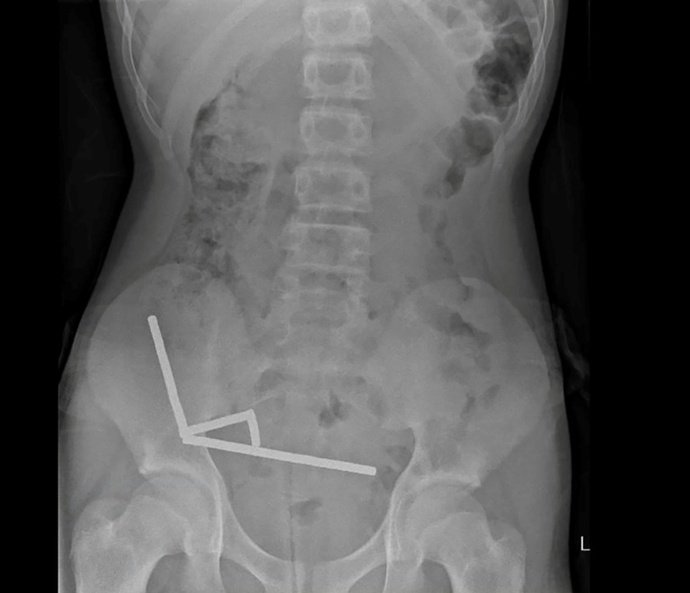

Die Magneten, die in Neuseeland seit Anfang 2013 verboten seien, seien auf der Temu-Plattform gekauft worden, teilten die Ärzte mit. Eine Röntgenaufnahme habe gezeigt, dass die Magneten sich in verschiedenen Bereichen des Darms aufgrund der Anziehungskraft zu vier geraden Linien zusammenklumpten. Den Ärzten zufolge starb durch die Kraft der Magneten an vier Stellen im Dünn- und Dickdarm Gewebe ab.